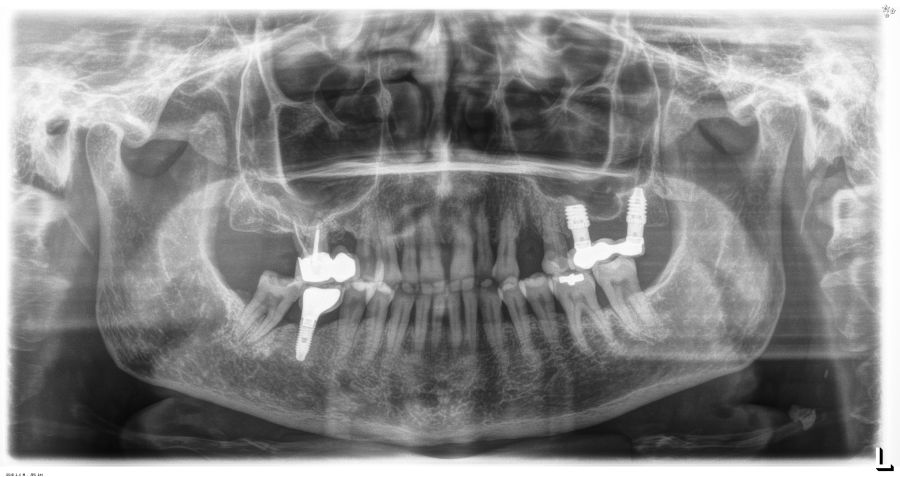

Todas las cirugías fueron realizadas por un único cirujano bajo anestesia local, tras un diagnóstico previo del lecho óseo mediante tomografía volumétrica (CBCT) procesada con un software específico de planificación implantológica (BTI-Scan III). La preparación del lecho implantario se llevó a cabo siguiendo la técnica de fresado biológico a bajas revoluciones descrita por Anitua y cols.19.

Los pacientes acudieron cada 6 meses a la realización de radiografías panorámicas y periapicales de control y sobre estas radiografías y se realizaron las mediciones necesarias para comprobar la estabilidad y pérdida ósea crestal de los implantes. Una vez obtenida la radiografía en formato digital fue calibrada mediante un software específico (Sidexis measure y Digora) a través de una longitud conocida en la radiografía como es el implante dental. Una vez introducimos la medida de calibración, el programa informático realizó un cálculo basado en esta medida para eliminar la magnificación, pudiendo realizar mediciones lineales exentas de este error. La pérdida ósea marginal se definió como la distancia entre el hombro del implante y el primer punto de contacto óseo visible sobre su superficie. En estas visitas se realiza además sondaje de los implantes y se anotaron los posibles signos y síntomas de periimplantitis o mucositis (sangrado espontáneo, al sondaje, inflamación o supuración).

En cuanto a la rehabilitación protésica, en todos los casos se utilizó una prótesis atornillada con transepitelial para prótesis unitaria. La supervivencia de las prótesis fue del 100%, sin encontrarse fracaso en ninguna de ellas al igual que los implantes, con un tiempo de seguimiento de tres años. Durante el primer año, en las visitas de control, ninguno de los implantes mostró sangrado al sondaje ni inflamación de los tejidos periimplantarios. La media de la pérdida ósea en este punto fue de 0,32 mm (+/- 0,60) y la media de la pérdida ósea distal de 0,31 (+/- 0,48). A los dos años, no se registraron tampoco signos inflamatorios en ninguno de los implantes y la pérdida ósea mesial del conjunto fue de media de 0,38 mm (+- 0,54) y la distal de 0,64 mm (+/- 0,70). En la última visita a los 3 años, los tejidos periimplantarios siguieron estables, sin signos de inflamación y la media de la pérdida ósea mesial fue de 0,40 mm (+/- 0,53) y la distal de 0,69 (+/- 0,55) (Figura 5). En las Figuras 6-12 se muestra uno de los casos incluidos en el estudio.